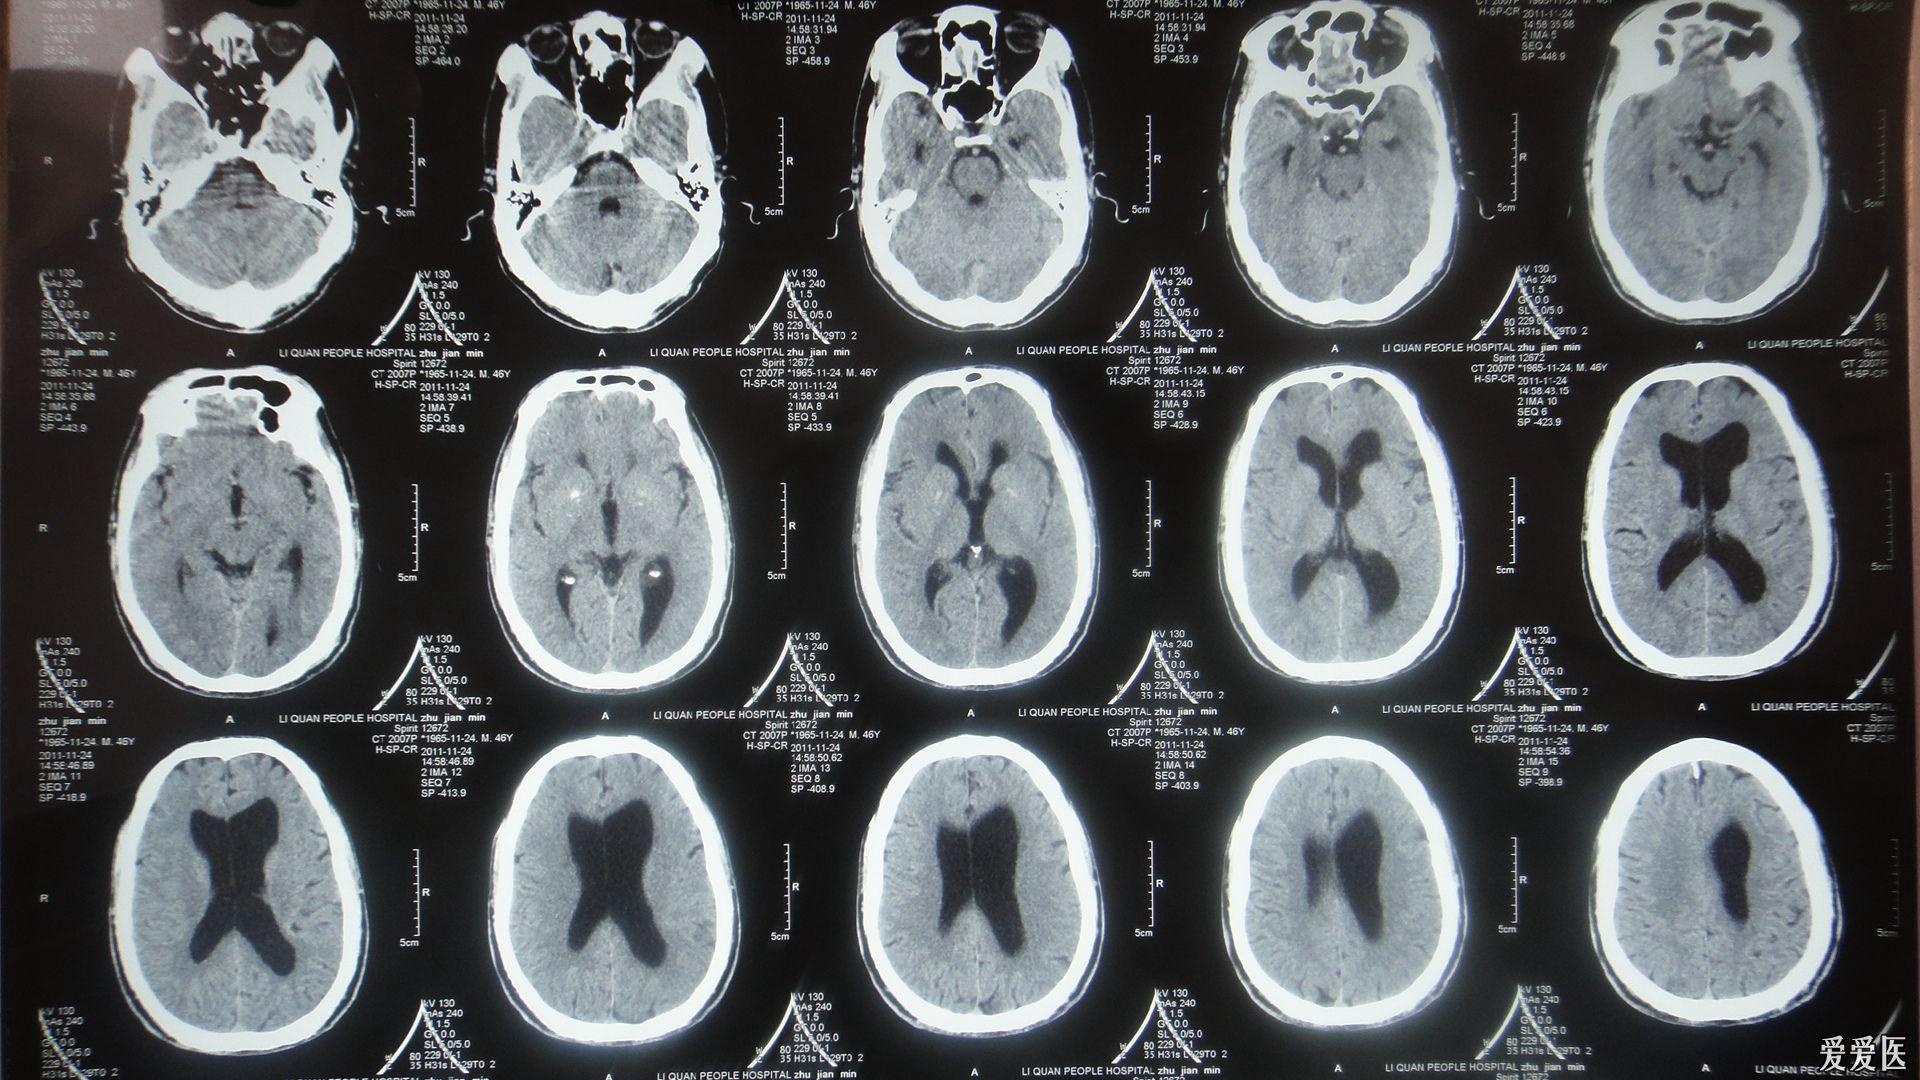

脑积水ct影像

成人正常脑ct和脑积水ct影像对比脑积水是由于颅脑疾患使得脑脊液分泌

查头颅ct:脑室系统扩张,脑积水(图-4)

术后复查头颅ct脑积水明显,胶干扰较大

【原创】典型的梗阻性脑积水